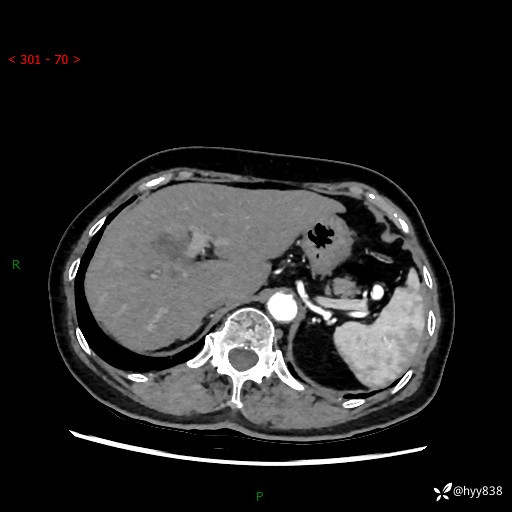

上腹部CT平扫+增强